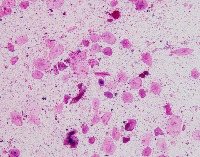

Medical Image Analysis: geckler3 could be used by healthcare professionals, researchers, and medical students to quickly and accurately identify White Blood Cells (WBC) and Erythrocyte-Hemoglobin Concentration (EHC) in clinical images, improving diagnosis and understanding of various blood-related conditions and diseases.

Blood Disorder Diagnosis Support: Implement geckler3 in diagnostic tools to assist doctors in identifying blood disorders, such as anemia or leukemia, by accurately analyzing WBC and EHC levels in blood images, helping with faster and precise diagnosis and treatment.

Biomedical Research: Utilize geckler3 in research laboratories for various biomedical and biotechnological studies to analyze large datasets of blood images, streamlining the process of data collection and analysis by automatically detecting WBC and EHC patterns.

Training and Educational Tool: Integrate geckler3 into educational platforms or applications to help medical and laboratory professionals, as well as medical students, learn and practice the identification of WBC and EHC in blood images, enhancing their skills and knowledge.

Remote Diagnosis Assistance: Employ geckler3 in telemedicine applications, allowing healthcare professionals to remotely access and analyze blood images for the presence of WBC and EHC, aiding in the diagnosis and management of blood-related conditions in areas with limited medical facilities.